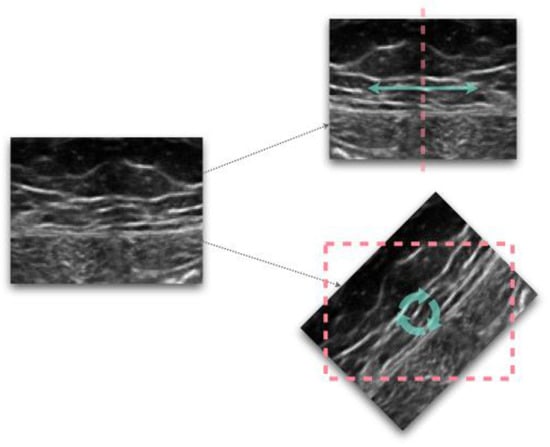

| Intensity-based/dimensional-based filtering | [3,6,12,17,28,54,70,86] |